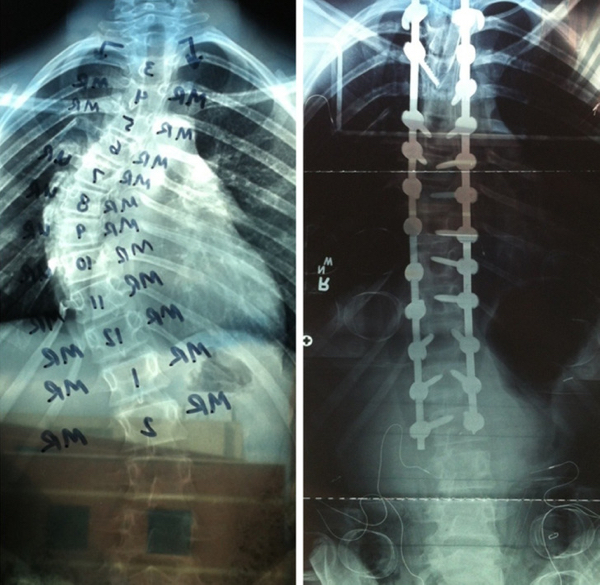

humanity 1380 Liked! 63 Disliked 0 People who vowed to change something about themselves are killing it (15 Photos) by: Adam In: Awesome, Humanity, Inspirational Jan 29, 2023 1380 Liked! 63 Disliked 0 1 “My little brother just had surgery on his spine. Here are some before/after X-ray pics.” LoganPS Like this post? 1380 Liked! 63 Disliked 0